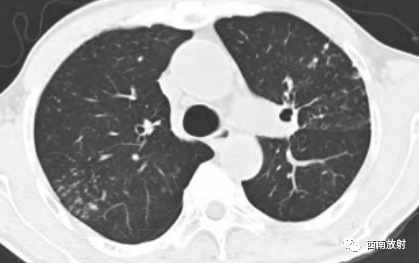

▲胞内分枝杆菌肺病,右肺中叶支气管扩张,右肺下叶小叶中心结节

▲女,66 岁,鸟分枝 杆菌肺病,右肺上叶支气管扩张伴多发小叶中心结节(树芽征)